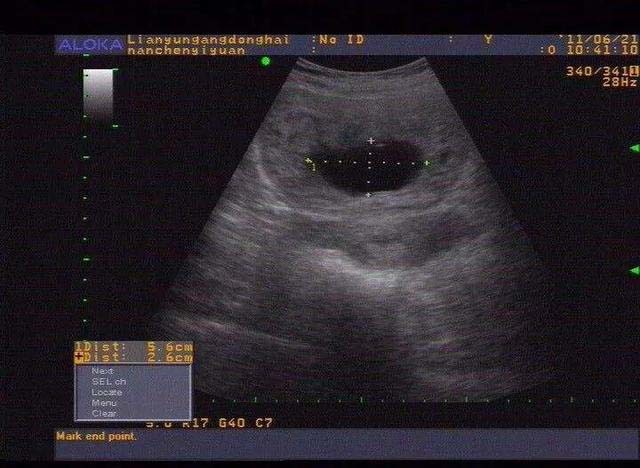

胎囊也叫孕囊或者妊娠囊,是胚胎最初的形态,将来宝宝就从这里长出来。 胎囊形成时间:孕30~40天。 一般月经比较正常的女性,停经35天 (孕5周)左右,通过B超就可以看到胎囊;孕6周时,孕囊的检出率为100%。 胎囊大小与孕周是相对应的,医生通常是通过B超检查的 孕囊大小 来推算孕周,这要比根据末次月经时间推算要准确。 1、异常胎囊 位置异常: 健康的胎囊应该在 卵黄囊内径一般在 35 mm,妊娠第 510 周逐渐增大,而 10 周之后逐渐减小。 卵黄囊的数量可用以判断多胎妊娠的羊膜囊性。通常来说,胚胎存活时卵黄囊数量与羊膜囊数量一致。因此,单绒单羊妊娠时可表现为 2 个胚胎、1 个绒毛膜囊、1 个羊膜囊和 1 个卵黄囊。孕囊大小对照表 怀孕4周:胎儿0.2厘米,此时的胎儿体积非常的小,用b超是看不到痕迹的。 怀孕5周:胎儿0.4厘米,通过b超可以看见胎囊,也或许可以看到胎芽。 怀孕6周:胎儿0.85厘米,通过b超可以看清楚胎囊,也可以看见胎芽及胎心跳。

孕囊胎儿大小对照表 1、4周:胎儿只有0.2厘米。 受精卵刚完成着床,羊膜腔才形成,体积很小。 超声还看不清妊娠迹象。 2、5周:胎儿长到0.4厘米,进入了胚胎期,羊膜腔扩大,原始心血管出现,可有搏动。 B超 可看见小胎囊,胎囊约占宫腔不到1/4,或可见胎芽。 3、6周:胎儿长到0.85厘米,胎儿头部、脑泡、额面器官、呼吸、消化、神经等器官分化,B超胎囊清晰 3、妊娠23周时HCG为mIU/m1; \n 4、妊娠34周时HCG为mIU/m1; \n 在妊娠4周左右HCG数值一般为隔天翻倍增长, 翻倍好不好也是判断妊娠是否正常4周:胎儿只有0.2厘米。 受精卵刚完成着床,羊膜腔才形成,体积很小。 超声还看不清妊娠迹象。 5周:胎儿长到0.4厘米,进入了胚胎期,羊膜腔扩大,原始心血管出现,可有搏动。 B超可看见小胎囊,胎囊约占宫腔不到1/4,或可见胎芽。 6周:胎儿长到0.85厘米,胎儿头部、脑泡、额面器官、呼吸、消化、神经等器官分化,B超胎囊清晰可见,并见胎芽及胎心跳。 7周

b超可见胎囊约占官腔1/2,胎儿形态及胎动清楚可见,并可看见卵黄囊。 9周:胎儿长到215厘米,胎儿头大于胎体,各部表现更清晰,头颅开始钙化、胎盘开始发育。b超可见胎囊几乎占满宫腔,胎儿轮廓更清晰,胎盘开始出现。 10周:胎儿长到2厘米,胎儿各器官均已形成,胎盘雏形形成。b超可见胎囊开始消失,月芽形胎盘可见,胎儿活跃在羊水中 。 11周:胎儿长到362 六周孕囊图片 来自:自媒体 怀孕6周b超胎囊显示图片能宝宝男女吗? 怀孕7周孕囊大小是否有双胎可能 怀孕7周孕囊大小是否有双胎可能 子宫前位 大小约为 60*45*48cm 宫内可见大小约为 40*17无回声囊 有胎心管博动 其内可见少许强光点 怎么么解读此B超单 谢谢 匿名用户 1440

怀孕4周孕囊大小多少正常 怀孕4周胎儿只有02厘米,受精卵刚完成着床,羊膜腔才形成,体积很小,超声还看不清妊娠迹象,此时还不能看到孕囊。 B超检查在妊娠5周后可以看见孕囊,怀孕6周时检出率达百分之百。 孕囊是原始的胎盘组织,被羊膜、血管网包裹的小胚胎,只能在怀孕早期见到。 月经28~30天规则孕囊来潮的妇女,停经35天,B超就可以在宫腔内看到孕囊: 并不能根据,B超胎囊的图片,不能根据数据及它们的形状来判断宝宝的性别的,这个是没有科学性的,也没有任何的意义,4个月以后去做B超可以查出男女了 有人说胎囊形状看性别很准 6 怀孕8周 孕囊大小 多大算正常 1、4周:胎儿只有02厘米。 受精卵刚完成着床,羊膜腔才形成,体积很小。 超声还看不清妊娠迹象。 2、5周:胎儿长到04厘米,进入了胚胎期,羊膜腔扩大,原始心血管出现,可有搏动。 B超可看见小胎囊,胎囊约占宫腔不到1/4,或可见胎芽。 3、6周:胎儿长到085厘米,胎儿头部、脑泡、额面器官、呼吸、消化、神经等器官分化,B超胎囊